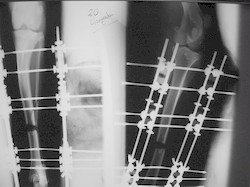

PRÁCTICAS CURSO DE FIJACIÓN EXTERNA PERFECCIONAMIENTO.

Elongacion.